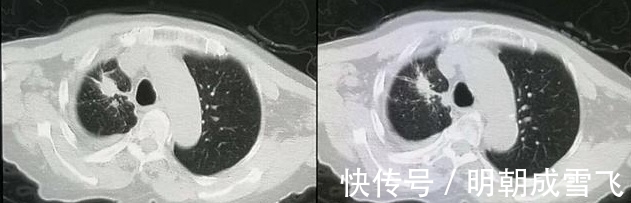

文章插图

这是一位80岁的老人,肺腺癌晚期,伴有胸膜转移和大量胸腔积液。

基因检测阳性,靶向治疗4年后复查:

病灶缩小,胸腔积液吸收,胸膜转移萎缩。

老人已经虚岁85了,从住院病历中看到,她一开始使用的是易瑞沙,后面是否配合其他药物并不清楚,因为后面几年都没有住院治疗。